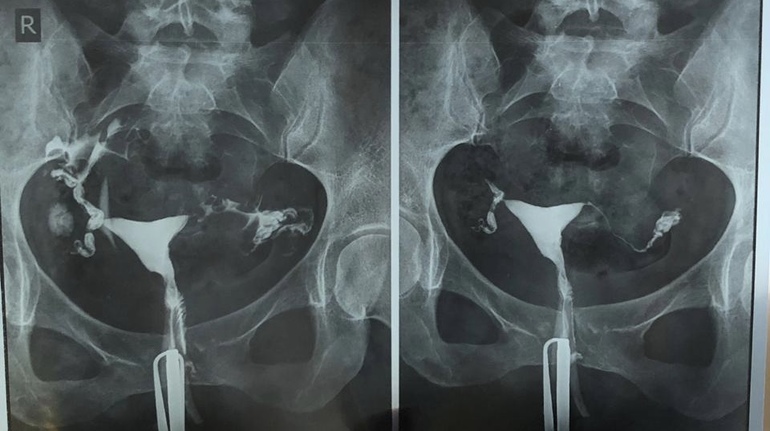

Гистеросальпингография: описание и фотографии